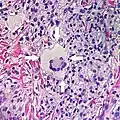

Multinucleated giant cells

- Specific forms of multinucleated giant cells include the Touton giant cell, which contains a ring of nuclei surrounding a central homogeneous cytoplasm, with foamy cytoplasm surrounding the nuclei.[29][30] The central cytoplasm (surrounded by the nuclei) may be both amphophilic and eosinophilic.[31]

Touton giant cell